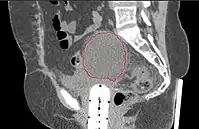

Work-Up

- CT of abdomen/pelvis typically not necessary, unless suspicion of extra-pelvic disease

- MRI is best modality for assessing myometrial invasion and cervical involvement, but provides no additional information if surgery is planned anyway

Lymphocele

- Seen postoperatively in up to 30% of GYN surgeries with pelvic/para-aortic LND

- Believed to arise from surgical transsection or inadequate ligation of draining lymphatics

- Lymphatic fluid may accumulate in various pelvic and retroperitoneal compartments

- Small lymphoceles typically resorb spontaneously

- Large lymphoceles may cause compression symptoms, and may result in abdominal distention, abdominal and pelvic pain, hydronephrosis, bladder dysfunction, constipation, tenesmus, edema of the ipsilateral leg and of the genitalia, and thromboembolism of iliac vessels

- Infection may cause fever, chills, and sepsis

- Symptomatic lymphoceles are typically managed initially with percutaneous CT-guided drainage, surgical therapy may be required

- Postoperative Lymphocele